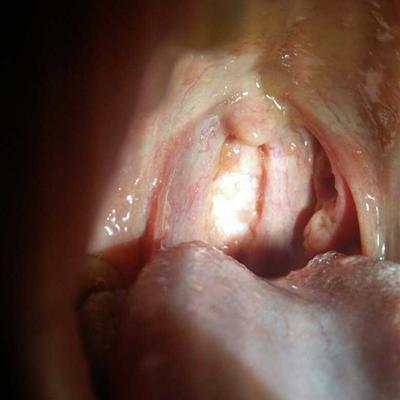

The tongue is a very important part of our body. It not only helps correct the pronunciation of sentences, but also distinguishes the taste. If the eyes are the windows of the soul, the tongue is the guard of the body. It blocks the invasion of things that are not conducive to us. The coating on the tongue is generally a thin layer,. The tongue is normally covered with a thin layer of white tongue coating. We all know that tongue coating is closely related to viscera. It can reflect the true and false of the cold and heat of the five viscera. What's the matter with the thick and greasy tongue coating? Let's talk about it now.

How is tongue coating thick greasy to return a responsibility?

First, there is water retention or phlegm in the body. White fur can appear in patients with water retention or phlegm in the body. Clinically, some patients with pleural effusion, ascites, slow nephritis, asthma, slow bronchitis, bronchiectasis, etc. are more common. There is dampness or phlegm retention in the body, which makes the tongue coating thick white or greasy.

Second: a variety of slow inflammatory infection, such as slow pelvic inflammatory disease, slow pyelonephritis, tuberculous meningitis, bone and joint tuberculosis, patients with tongue coating is slightly thicker than normal, or thin white greasy coating. It may be that patients in the recovery stage of the disease will also show white moss, indicating that patients in the early stage of respiratory tract infection, acute bronchitis, pneumonia and so on.

Thirdly, the stomach is hot, which can present the disorder of noise in the stomach, elimination of grain and good hunger. The stomach is hot, which can show the symptoms of bitter mouth, thirst, constipation and so on. Even more, it will cause stomach yin deficiency. Stomach fire inflammation, can cause stomach qi on the inverse, visible disgust, vomiting adverse sour bitter yellow water and other diseases. If the stomach fire is inflamed along the meridians, or it is toothache and gingival swelling, or it is bleeding. If the heat burns the head of the stomach, the blood will overflow and hematemesis will occur.